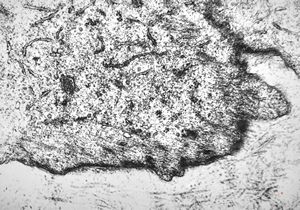

M,56y. | amyloidosis - tendon